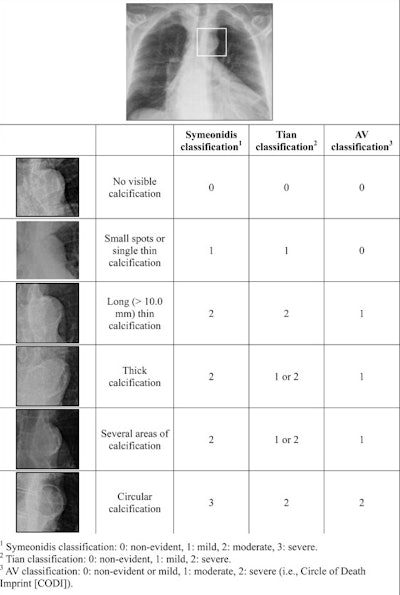

All patients had an upright antero-posterior chest x-ray acquired within three months before amputation, which were jointly read by two researchers. They categorized AC into three groups using three classification systems: none or mild (no visible calcification or a single focal calcification measuring < 10 mm), moderate (thick or elongated calcification measuring ≥ 10 mm, or multiple focal calcifications), and severe (circumferential or near-circumferential calcification).

Grading of radiological findings of aortic calcifications according to the earlier described Symeonidis and Tian classification systems and the novel AV classification system. 1 Symeonidis classification: 0: non-evident, 1: mild, 2: moderate, 3: severe. 2 Tian classification: 0: non-evident, 1: mild, 2: severe. 3 AV classification: 0: non-evident or mild, 1: moderate, 2: severe.JVS-Vascular Insights